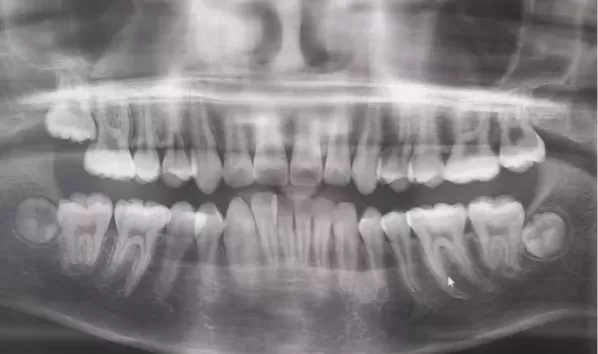

Rayons X avant le traitement

[Radiographie panoramique/Céphalogramme latéral]